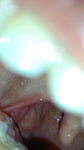

Здравствуйте, дорогие врачи. Были новообразования слева и хронический тонзиллит. Слева удалили и прочистили и справа тоже почистили все казеолы, назначены было лечение тонзиллор таблетки, лимфиазот, Кандид. Твкже полоскала ромашкой и физиотерапии уз аппаратом + промывание лакуны. Воспаление прошло. Но ощущение комп в горле справа осталось. Сдала посев и зевы на микрофлору думаю что бактерия ещё есть и ничего в анализах не нашлось. Нормальная микрофлора. Справа при попытке смазывания на горле заметил как шарик бугорочек, который и замечает пациент, скажите что за шарик, фото прикладываю. Может ли это быть раком?

Здравствуйте, Элина. Это не рак! Это часть лимфоидной ткани миндалин. Вариант нормы. В лечении не нуждается. Все правильно Вы делали- прочистили миндалины тонзиллором, периодически так нужно делать- поддерживать дренаж миндалин. Оставайтесь здоровой.